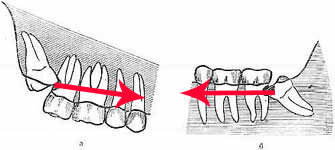

Сейчас есть звуковые, повышающие приводы, есть ультразвук, есть специальные лекарства, нормальная анестезия и, самое главное — достаточная практика, чтобы провести удаление даже очень сложного зуба мудрости за 7-17 минут. Скажу даже больше — если операция затягивается больше, чем на 30 минут — это повод задуматься о квалификации доктора. Это происходит очень-очень редко и, если происходит у меня, то мне потом очень стыдно перед всеми.

Так, между левой и правой фотографиями разница — не более 15 минут. Случай интересный, подробности здесь>>